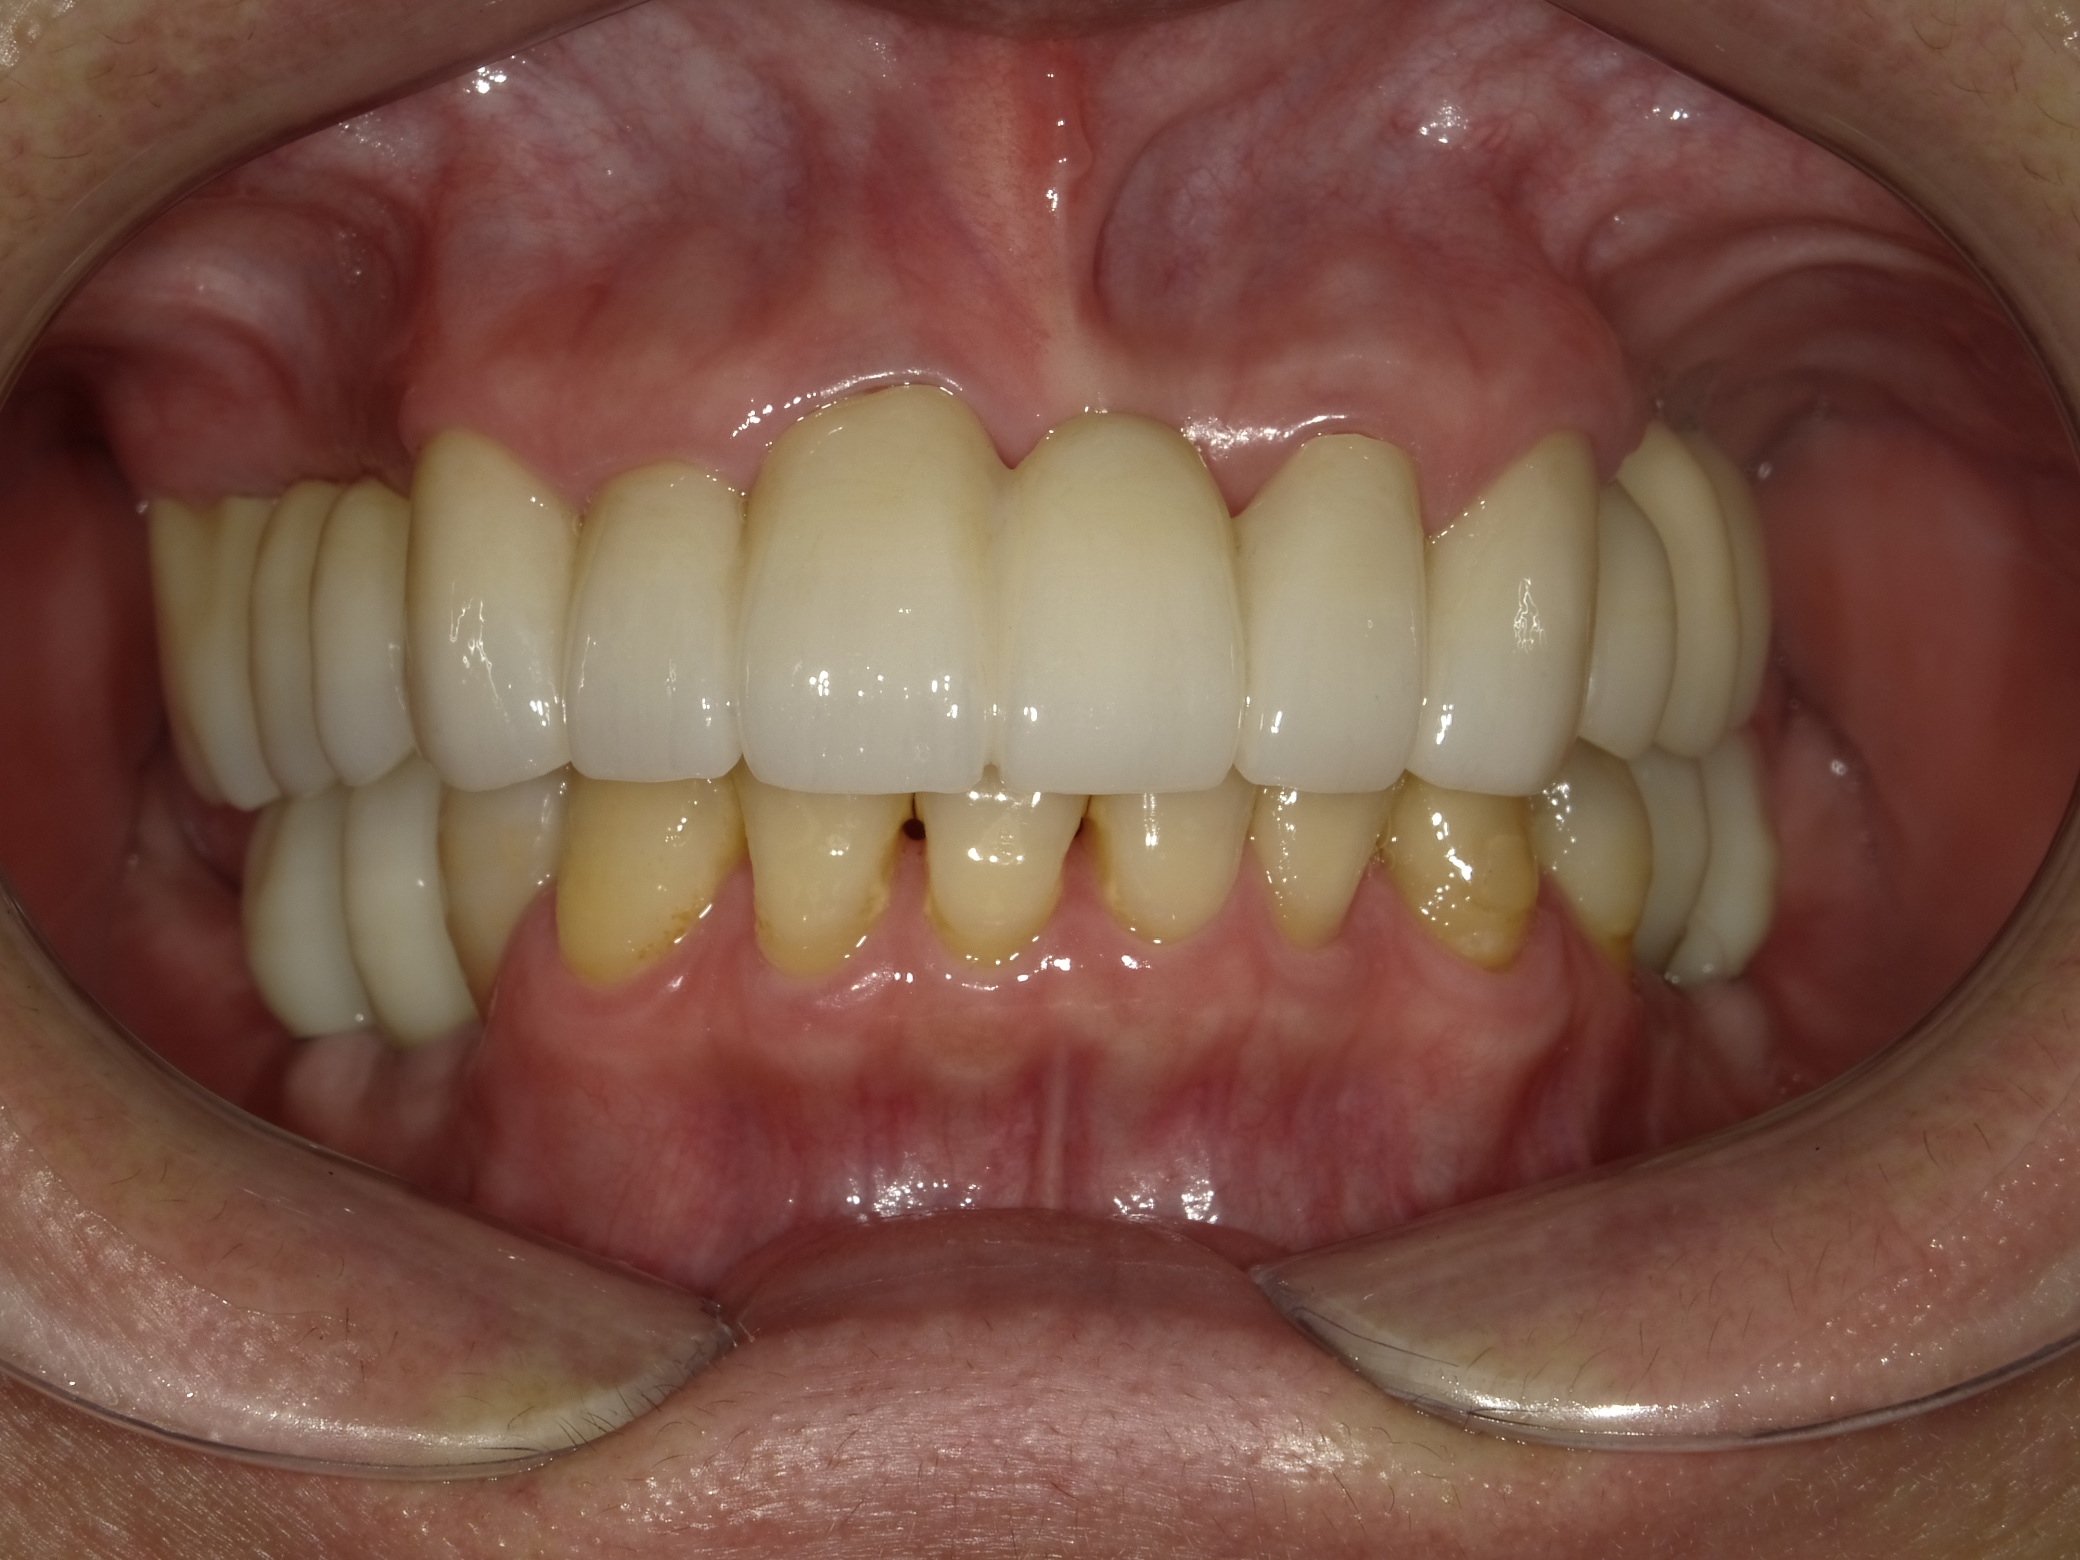

AFTER

主訴

全体的に見た目を綺麗にしたい。奥歯でしっかり噛みたい。

診断名・主な症状

臼歯部欠損

年齢

65歳

治療内容

インプラント埋入(左下5・6,右下5・6,左上4・6)

サイナスリフト(左上4・6)

ジルコニアBr(右上6−左上3)

E –MAX CAD(右下4)

セラミックインレー(左下4)

治療期間/

通院回数

約1.5年/約20回

費用

インプラント治療 約2,000,000円

その他被せ物治療など 約1,000,000円

合計 約3,000,000円

*いずれも税込

インプラント治療の

リスク・副作用

定期的なメインテナンスを行わない場合、インプラントが脱落する可能性があります。被せ物は経年的な劣化で欠ける可能性があります。